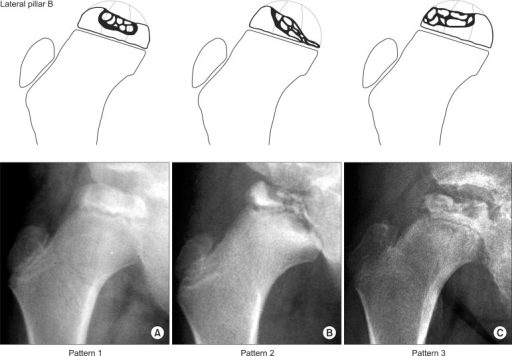

Osteocondrosis de la cabeza del fémur que afecta a niños, caracterizada inicialmente por necrosis epifisaria o degeneración seguida de regeneración o recalcificación.

Legg-Calve-Perthes disease is a childhood condition that affects the hip, where the thighbone (femur) and pelvis meet in a ball-and-socket joint. Legg-Calve-Perthes disease occurs when blood supply is temporarily interrupted to the ball part (femoral head) of the hip joint. Without sufficient blood flow, the bone begins to die — so it breaks more easily and heals poorly.

La enfermedad de Legg-Calvé-Perthes consiste en una necrosis isquémica de la epífisis femoral proximal en el esqueleto del niño de etiología desconocida. Fue descrita de forma simultánea e independiente por Legg, Calvé y Perthes en la primera década del siglo xx.